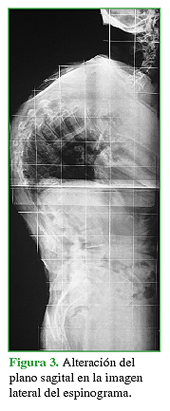

Se han descrito múltiples alteraciones espinales principalmente relacionadas con trastornos del equilibrio tanto en el plano coronal como en el sagital (Figuras 1,2,3).

En este tipo de pacientes, las deformidades posturales asociadas están relacionadas con el aumento del tono de los músculos axiales y de las extremidades acompañado de la disminución progresiva de la propiocepción neuronal.3,4 El 3-12,9% tiene camptocormia, se trata de una postura anormal con una marcada flexión de la columna toracolumbar que se incrementa con el tiempo y la fatiga durante el día y al caminar. Es una insuficiencia postural progresiva que disminuye en decúbito supino o en posición sentada, o se corrige cuando el paciente con EP se apoya contra una pared. Este cuadro se asocia no solo con la EP, sino que también puede observarse en pacientes con enfermedades por otras causas, como miopatías, miositis, atrofia multisistémica y trastorno de conversión. Por lo general, no hay anormalidades radiográficas o cambios estructurales que se refieran a ese tipo de disfunción neuromuscular.5